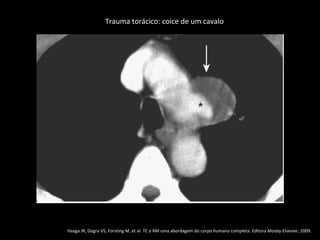

Trauma torácico: coice de um cavalo

Haaga JR, Dogra VS, Forsting M, et al. TC e RM uma abordagem do corpo humano completa. Editora Mosby-Elsevier, 2009.